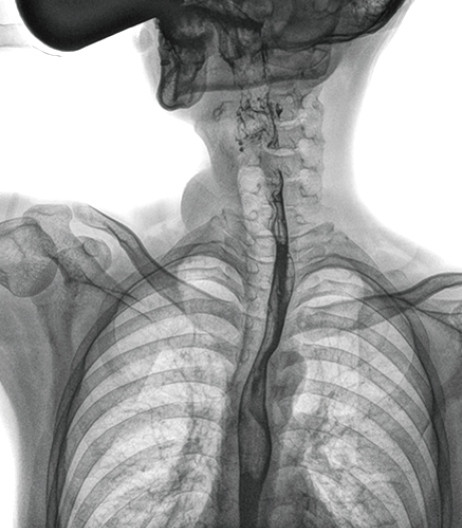

动态DR能够实现大幅面透视,瞬时高清点片等。在食管造影检查中,由于吞咽钡剂后,造影剂流速非常快,在一个大幅面上方便观察食管的病变。瞬时点片,可以实时捕捉到病变部位的影像,从而可以快速做出诊断。普利德多功能动态DR拥有17×17英寸超大视野,一次曝光即可显示整个食管,更方便观察食管的病变,确定病变的范围,对诊断和治疗有重要参考价值。

与过去的数字胃肠机比较,动态DR图像分辨率高,对食管的全景观察,局部粘膜破坏、中断,管腔狭窄以及病灶范围的显示清晰度明显更优。

上消化道造影高清图像